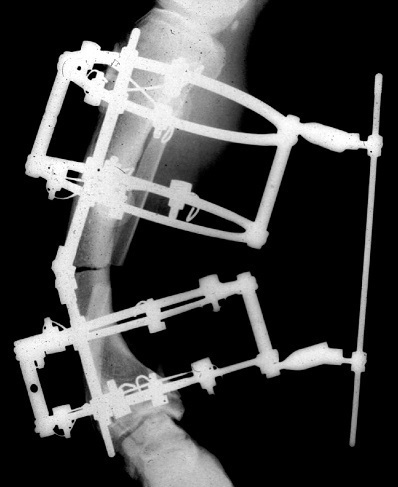

装具による固定、イリザロフ法(レントゲン)

たとえば、低身長の方の場合は、骨を人工的に切ることによりわざと骨折の状態を作り出します。さらに、下図のような装具を用いて外から固定する(「創外固定」といいます)ことにより、一定の力を加えていきます。装具を用いるのは、きちんと正しい方向に骨を伸ばしていくためです。そこから、骨が徐々に伸びていきます。

この方法により、奇形や事故などにより変形してしまった骨をまっすぐに治すこともできます。この際に、一定の方向に適切な張力をかけ続けて正しい方向に伸ばしていくことが大切です。そのために装具を使います。